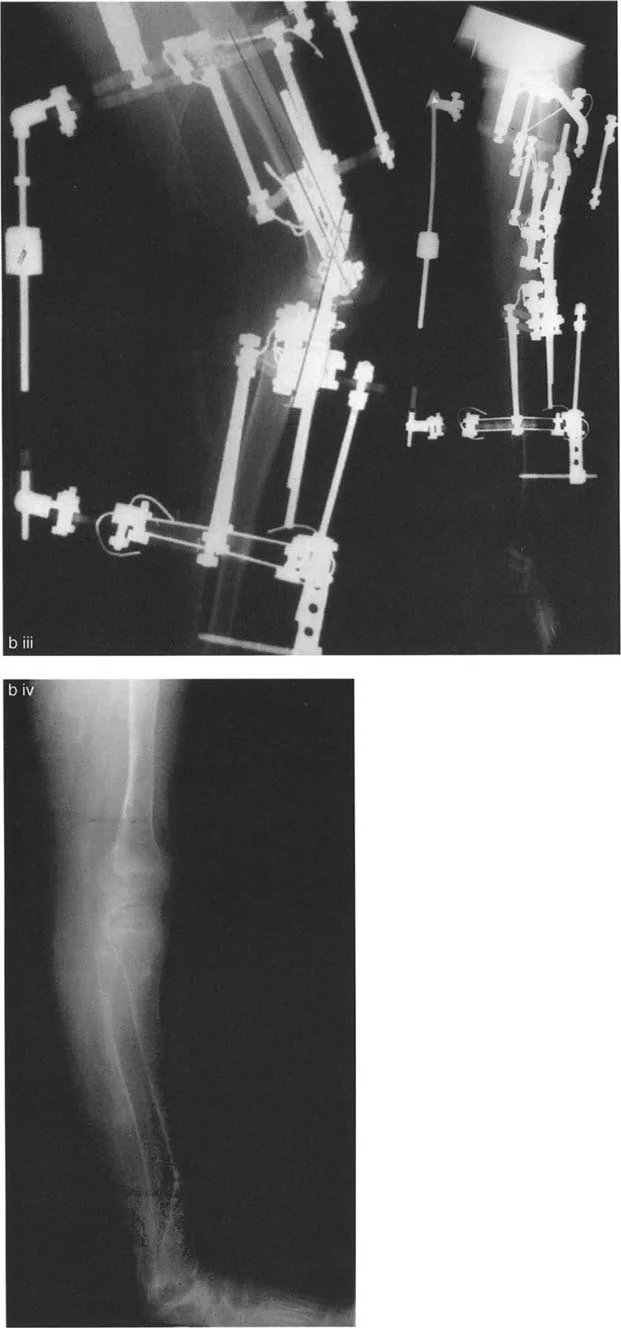

تتضمن جراحة قطع العظم قطع العظم (عادة عظم الفخذ أو الساق) وإعادة تشكيله لتغيير محاذاة المفصل. يمكن أن يكون القطع:

- قطع العظم بالوتد المفتوح (Opening Wedge Osteotomy): يتم عمل قطع في العظم ثم فتح فجوة صغيرة تُملأ غالبًا بطعم عظمي، مما يطيل الجزء المعني من العظم ويصحح المحاذاة.

- قطع العظم بالوتد المغلق (Closing Wedge Osteotomy): يتم إزالة جزء صغير من العظم على شكل وتد، ثم تُغلق الفجوة وتُثبت العظام، مما يقصر الجزء المعني ويصحح المحاذاة.

يتم تثبيت العظام بعد القطع باستخدام صفائح ومسامير أو تثبيت خارجي، لضمان التئام العظم في الوضعية الجديدة.

- مخاطر العصب الشظوي: التصحيح الحاد للانحراف الأروح في الساق قد يؤدي إلى شد العصب الشظوي، مما قد يسبب إصابة العصب أو متلازمة الحيز. قد يُنصح بإجراء تحرير وقائي للعصب الشظوي وقطع اللفافة (Fasciotomy) في التصحيحات الكبيرة، أو استخدام التصحيح التدريجي بالتثبيت الخارجي.

- التصحيح التدريجي: في حالات تحدد الحركة الشديدة أو المعقدة، قد يكون التصحيح التدريجي باستخدام التثبيت الخارجي هو الخيار الأكثر أمانًا.

اعتبارات جراحية إضافية